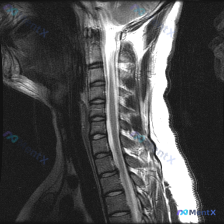

- 影像只有颈椎MRI T2加权矢状位

- 看图像细节,发现了几个比“侧弯”更直接的征象